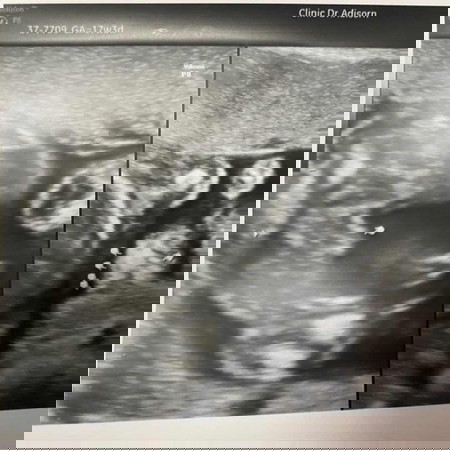

ไปซาวมา 17w 3 ช หรือญ แม่ๆช่วยดูหน่อย

กลีบๆผู้หญิงนะคะ